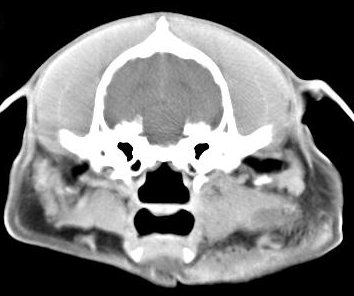

Diagnóstico neurológico | ||||||||||

imágenes de TC en el perro | ||||||||||

ejemplo de imágenes de TC en el perro. Nótese la celulitis en la región parotídea izquierda | ||||||||||